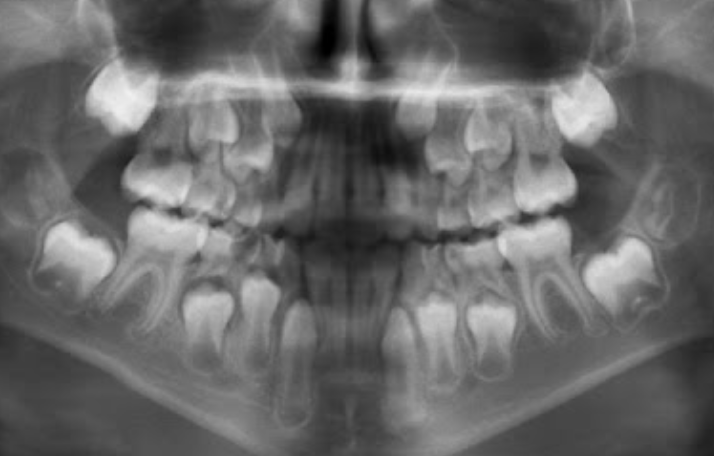

Permanent lower incisors present? Yes, so definitely 6-7

Permanent upper Incisors not erupted yet. Therefore not 7-8 y.o.

Conclusion = 6 y.o